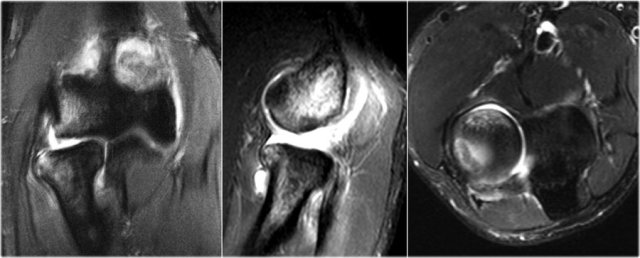

The MR-arthrogram confirms the osteochondral lesion.

There is gadolinium in between the humerus and the osteochondral lesion which indicates that it is unstable.

If you don't have gadolinium, look for joint fluid undercutting the fragment.

There is a loose body in the posterior recess of the radiocapittelar joint.

Notice also the fragmentation as seen on the axial image.

The MR-arthrogram shows some bone marrow edema on the coronal view.

The sagittal T1W-image shows subchondral bone abnormality, but not much of a fragment.

There is some cartilage thinning, but not a defect.

This is obviously a stable fragment and there were no loose bodies.